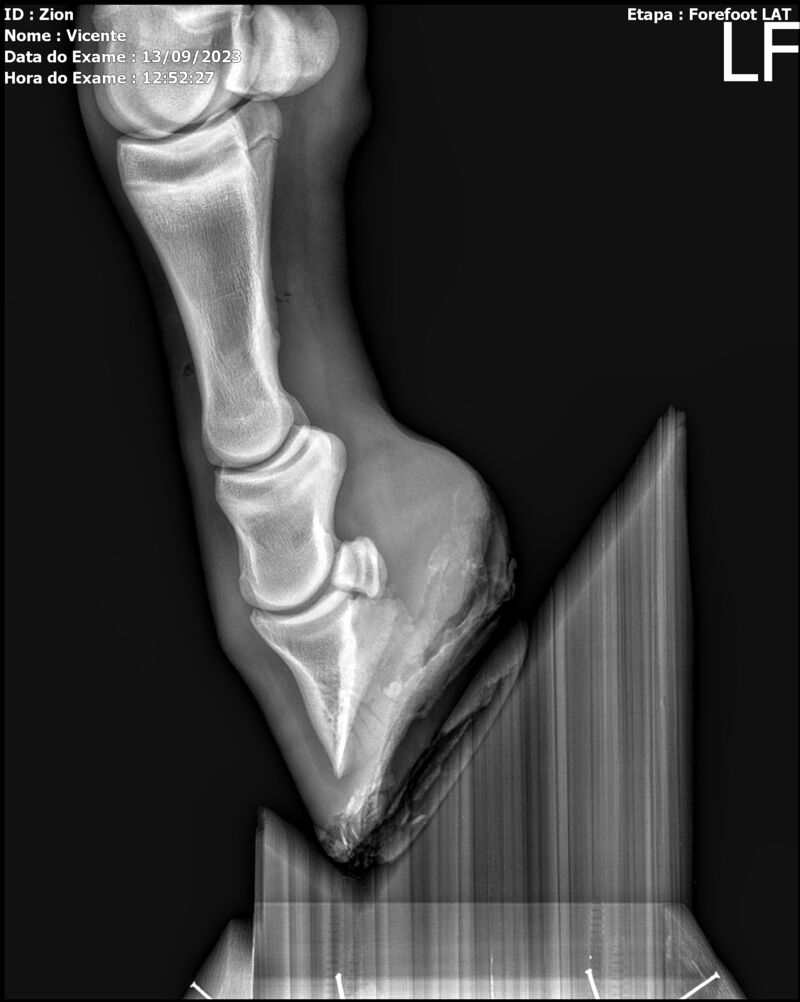

ZION ZC

Raça: BRASILEIRO DE HIPISMO

Sexo: MACHO - POTRO

Nascimento: 17/12/2022

Altura Aproximada: 1,51

Pel.: CASTANHO

Registro: EM AND

Vend.: VICENTE CONTE

Local : PORTO FELIZ/SP